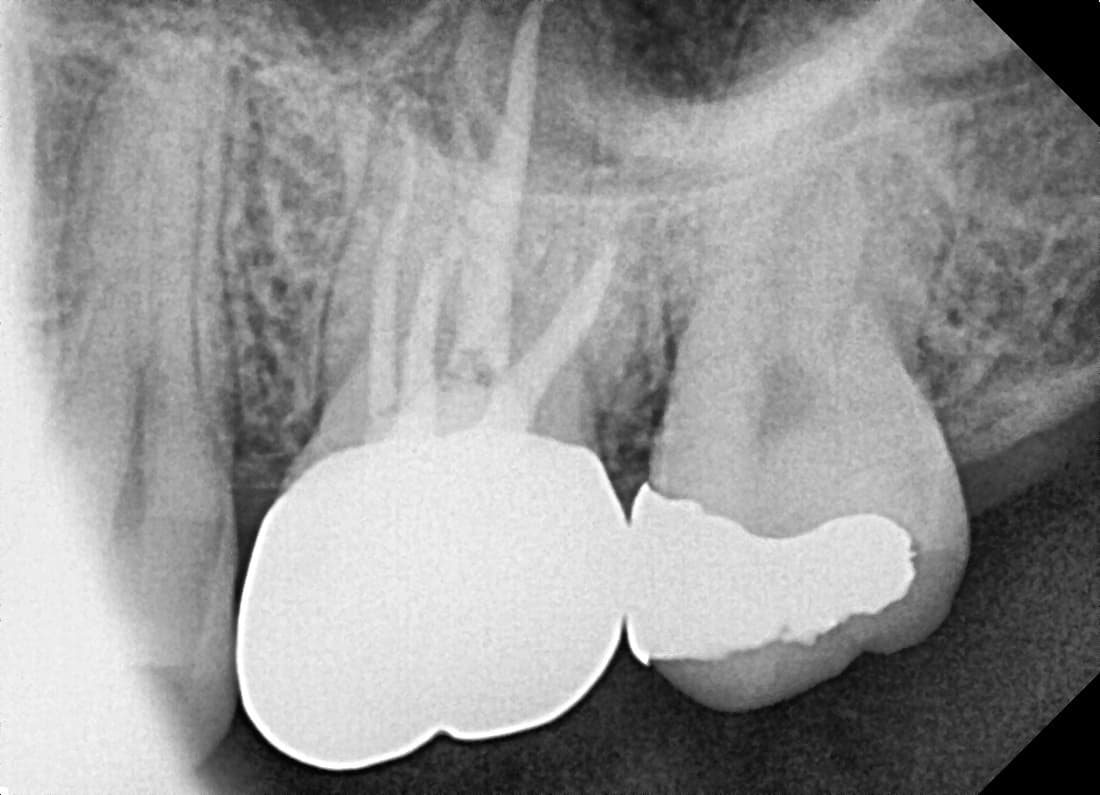

Root Canal Re-treatment

Molar recurrence after treatment elsewhere

Before

After

Complete healing 1 year 9 months after finding additional canal through re-treatment